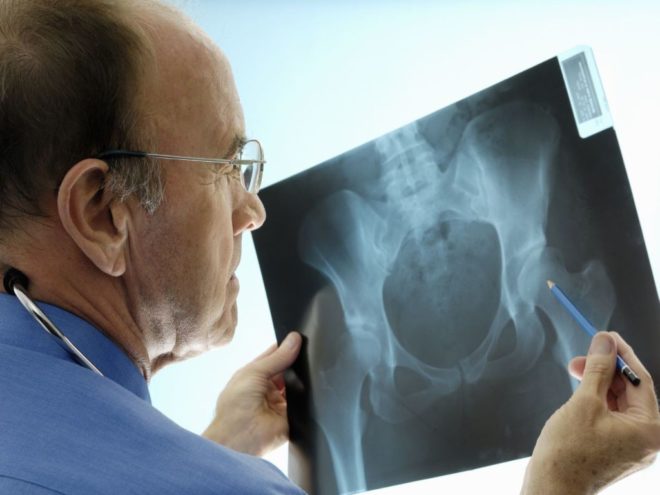

- A belépő a mentők által kijelölt személy az X-ray (a két vetület). Az így kapott határozza meg a pontos természetét csípőtörés.

Jellemzői műtéti és konzervatív kezelés

Ha van egy törés, az alsó végtagok, mint a combnyak komplex formában nem mindig kell műtét. Ezen kívül vannak olyan esetek, amikor a beteg valamilyen okból egészségügyi ellenjavallt a műveletet.